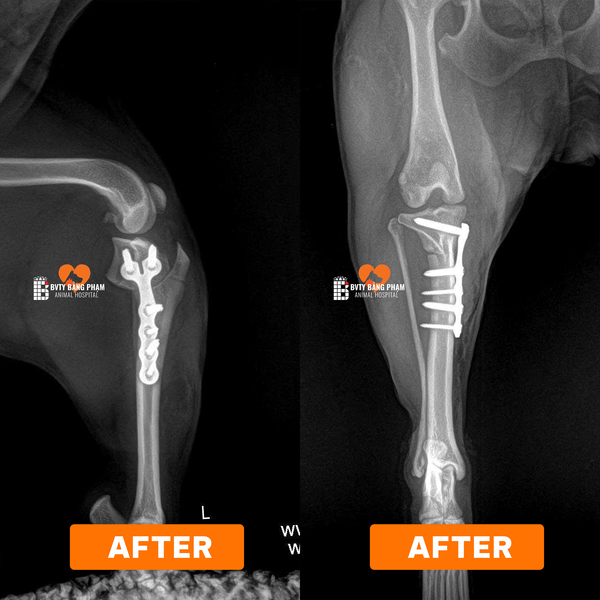

Tại Bệnh viện Thú Y Bằng Phạm, đội ngũ bác sĩ chuyên khoa chỉnh hình đã tiếp nhận và điều trị nhiều ca đứt dây chằng chéo trước (CCL) bằng kỹ thuật TPLO (Tibial Plateau Leveling Osteotomy) — một trong những phương pháp hiện đại và hiệu quả nhất hiện nay. Theo tài liệu chuyên môn, TPLO giúp thay đổi góc của mặt trượt xương chày, từ đó loại bỏ lực trượt (tibia thrust) lên khớp gối và tái lập sự ổn định mà không cần “cố gắng tái tạo hay khâu dây chằng” như cách truyền thống.

Phẫu thuật TPLO: cắt một đoạn xương chày theo hình bán nguyệt, xoay đoạn này để tạo góc mới phù hợp, sau đó cố định bằng bản kim loại và vít